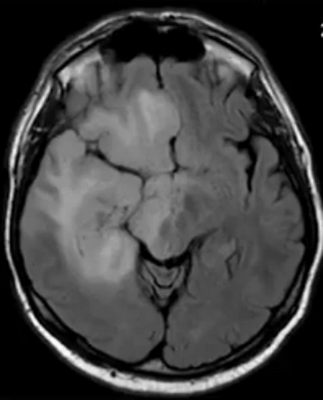

Глиобластома на МРТ головного мозга без контраста

В зависимости от типа новообразования отличается его внешний вид. Изучая снимки, врач может лишь предположить природу основных вариантов опухолей по характерным признакам:

- глиобластомы — злокачественные опухоли, которые отличаются высокой скоростью роста и склонностью к инвазии. Выглядят на снимках, как образования неправильной формы, с нечеткими фестончатыми контурами и выраженным перифокальным отеком. Дают выраженный масс-эффект, смещают головной мозг в полости черепа, повреждая его на отдалении от своего местоположения;